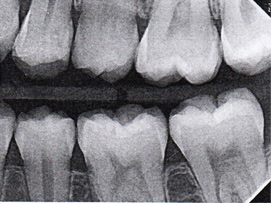

Fig 3. Three thin soft dental picks were used simultaneously for SDF proximal surface saturations in a teenaged patient (Fig 3). After 60 seconds, the treated regions were covered with 5% fluoride varnish (Fig 4). A comparison can be seen of pre-SDF-treatment bitewing films (Fig 5) and 8-month post-SDF bitewing films (Fig 6) for the patient shown in Fig 3 and Fig 4. Radiolucencies were similar or improved, except for contact of maxillary first and second molars.

Fig 5. Three thin soft dental picks were used simultaneously for SDF proximal surface saturations in a teenaged patient (Fig 3). After 60 seconds, the treated regions were covered with 5% fluoride varnish (Fig 4). A comparison can be seen of pre-SDF-treatment bitewing films (Fig 5) and 8-month post-SDF bitewing films (Fig 6) for the patient shown in Fig 3 and Fig 4. Radiolucencies were similar or improved, except for contact of maxillary first and second molars.

Figure 5